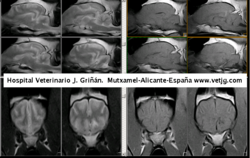

imágenes de resonancia de una hemorragia cerebral en un chow-chow |